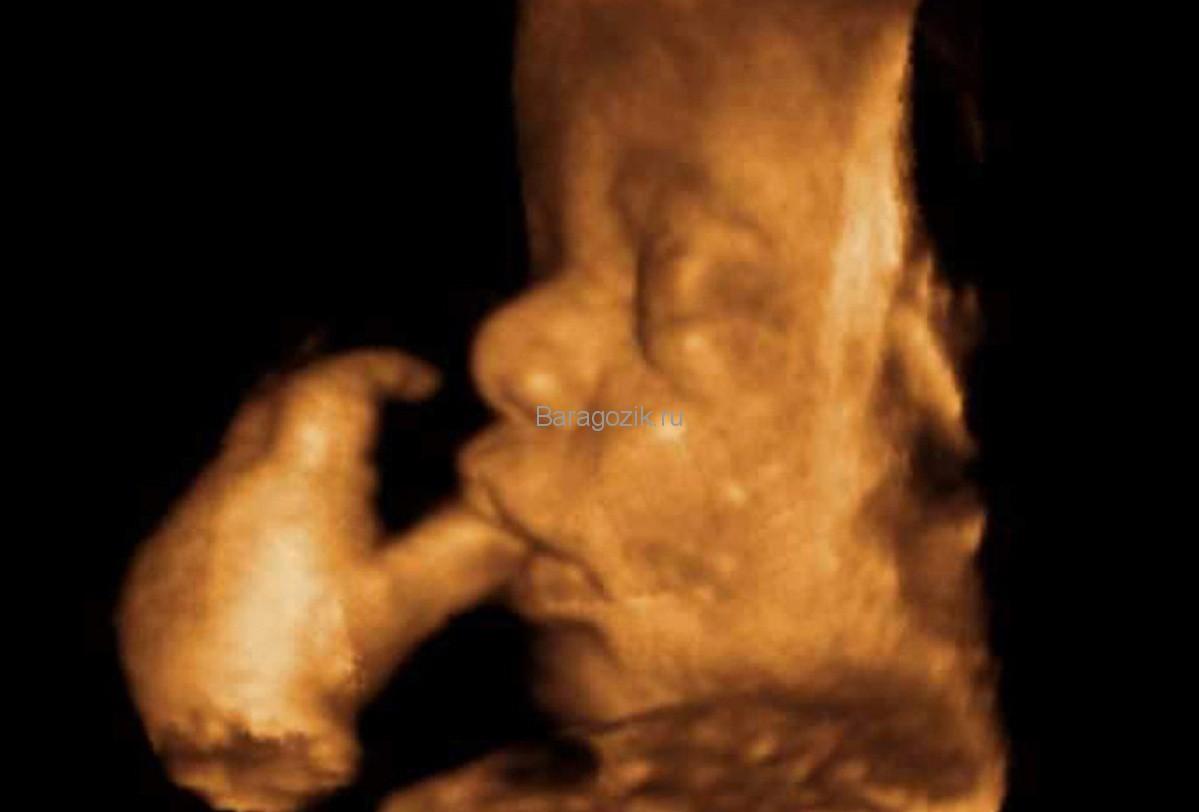

35 -я неделя беременности является самой сложной за весь период вынашивания, . . . Фото галереи . . . Развитие плода . На 35 акушерской неделе вес малыша составляет 2300-2600 г, длина тела - 45-48 см . . . .

35 неделя развития плода на фото Развитие плода на 35 неделе беременности Плод на 35 неделе беременности уже достаточно хорошо развит .